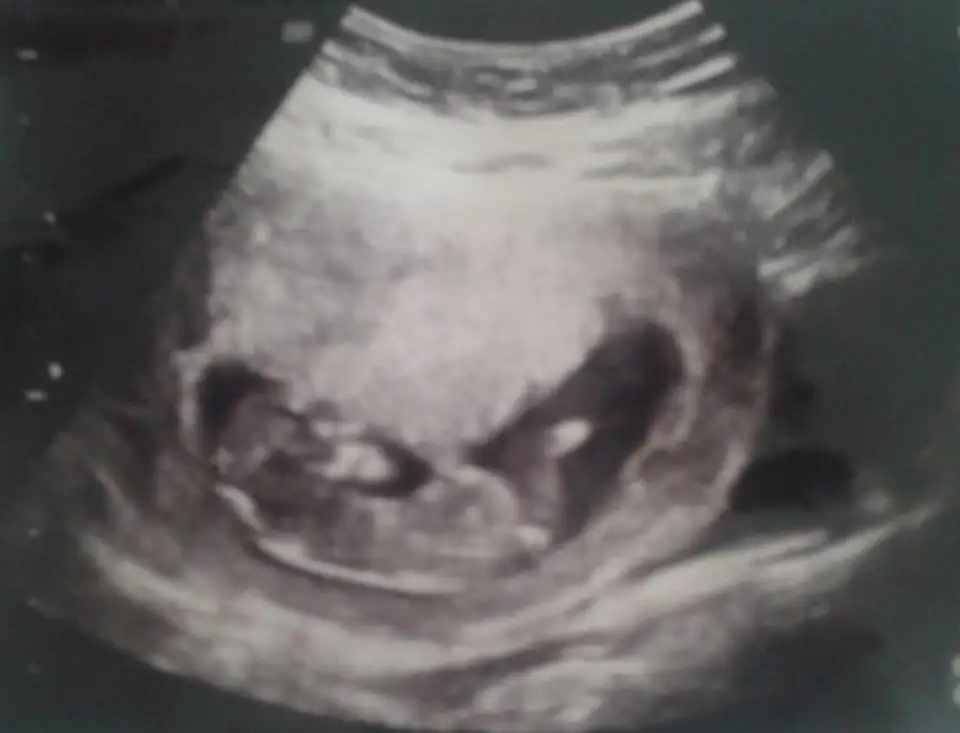

Erkek cnm benimkibaslarda kiz felan gibi dendi ama 18.haftada kesinlesmisti erkek olduğu sizin ki ney

Aa bilmiyodum bak. Doğru bilmişim seninkini.Erkek cnm benimkibaslarda kiz felan gibi dendi ama 18.haftada kesinlesmisti erkek olduğu sizin ki ney

Aa bilmiyodum bak. Doğru bilmişim seninkini.Sağlıkla kucağına al.Benimki kız

Benim kesem muz gibi, henuz net bilmiyrm cinsiyetini, doktor kiza benzettiBir kişi cikipta demedi ki kese muz gibi ve kızım olucak ..